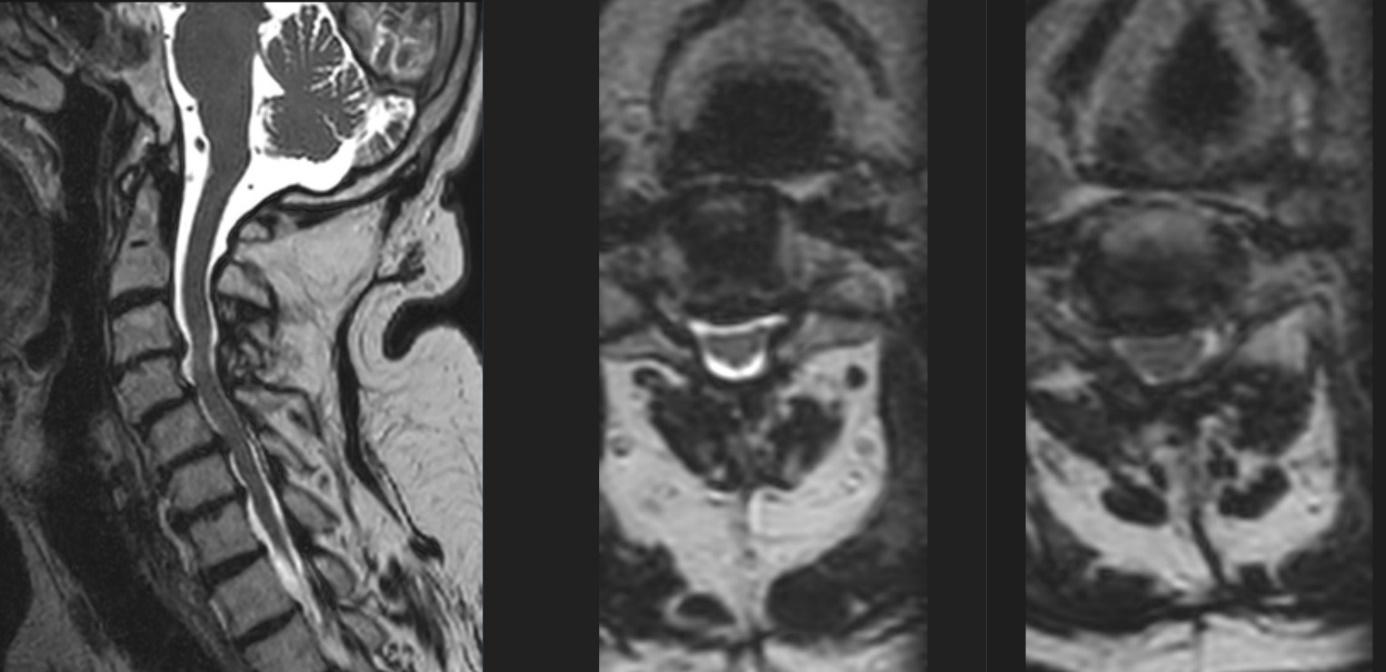

36 SRKF: Den degenerativa halsryggen